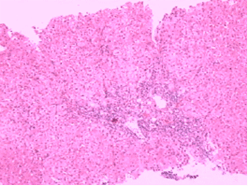

3、組織學特徵:黏膜下靜脈擴張,無或僅有輕微炎性細胞浸潤為其特徵性表現。其他還有黏膜下小動靜脈壁增厚,靜脈動脈化。黏膜橫斷面毛細血管面積較正常增大。胃黏膜毛細血管發育不良,散在裸露於胃腔內,表面無上皮組織覆蓋。胃黏膜小動脈變直,螺鏇度減輕。小血管注射研究發現,黏膜下動靜脈分流廣泛開放,電鏡觀察顯示毛細血管顯著擴張,內皮小孔擴大,血管內皮與基底膜連線不緊密,出現間隔,血管基底膜不連續,毛細血管基膜與上皮細胞基膜之間距離變寬,上皮細胞腫脹變性。紅細胞從破損的上皮處外滲,並出現於上皮間隙之間。因內鏡活檢取材小且表淺,僅有50%的活檢標本病理見有毛細血管擴張。